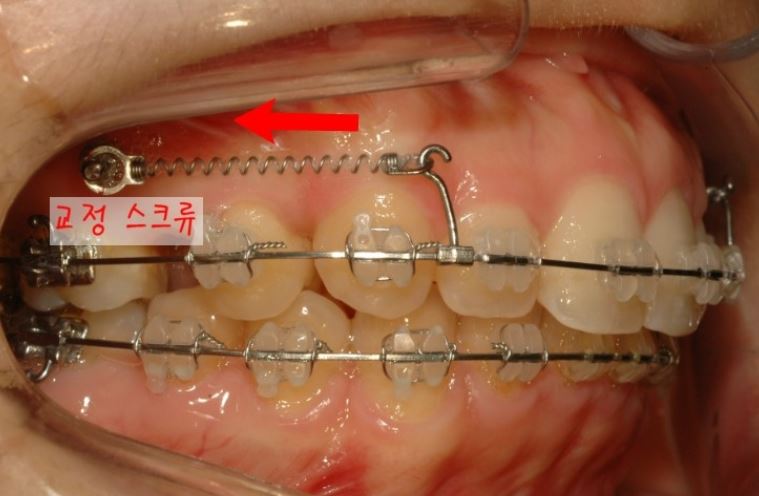

특히 교정 스크류를 사용하여

뒤로 당기는 경우

브라켓과 치아 사이에

적절한 마찰이 잘 결리기

때문에 치아들이 서로 틀어지지 않고

방향을 유지하면서

빈 공간으로 이동을 잘 합니다.

발치한 자리로 앞니가

가지런하게 잘 이동한 뒤 모습입니다.